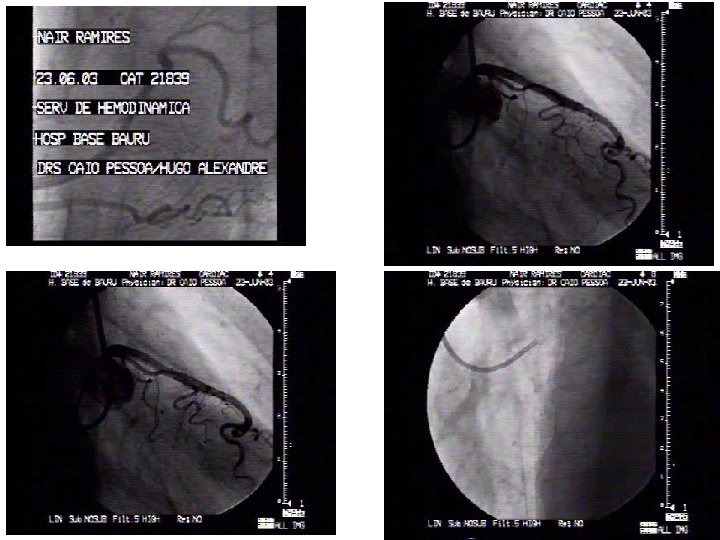

Nair C. Rodrigues Sexo - feminino Idade – 63 anos HAS Hipercolesterolemia Unidade Coronária 10/02/2003 IAM não Q - anterior

Viabilidade? Estenose residual é limiante de fluxo? Um ou mais vasos? Risco de novo evento?